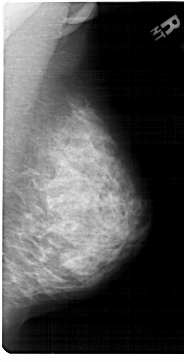

A_1453_1.RIGHT_MLO

RIGHT_MLO LINES 6871 PIXELS_PER_LINE 3496 BITS_PER_PIXEL 12 RESOLUTION 43.5 NON_OVERLAY